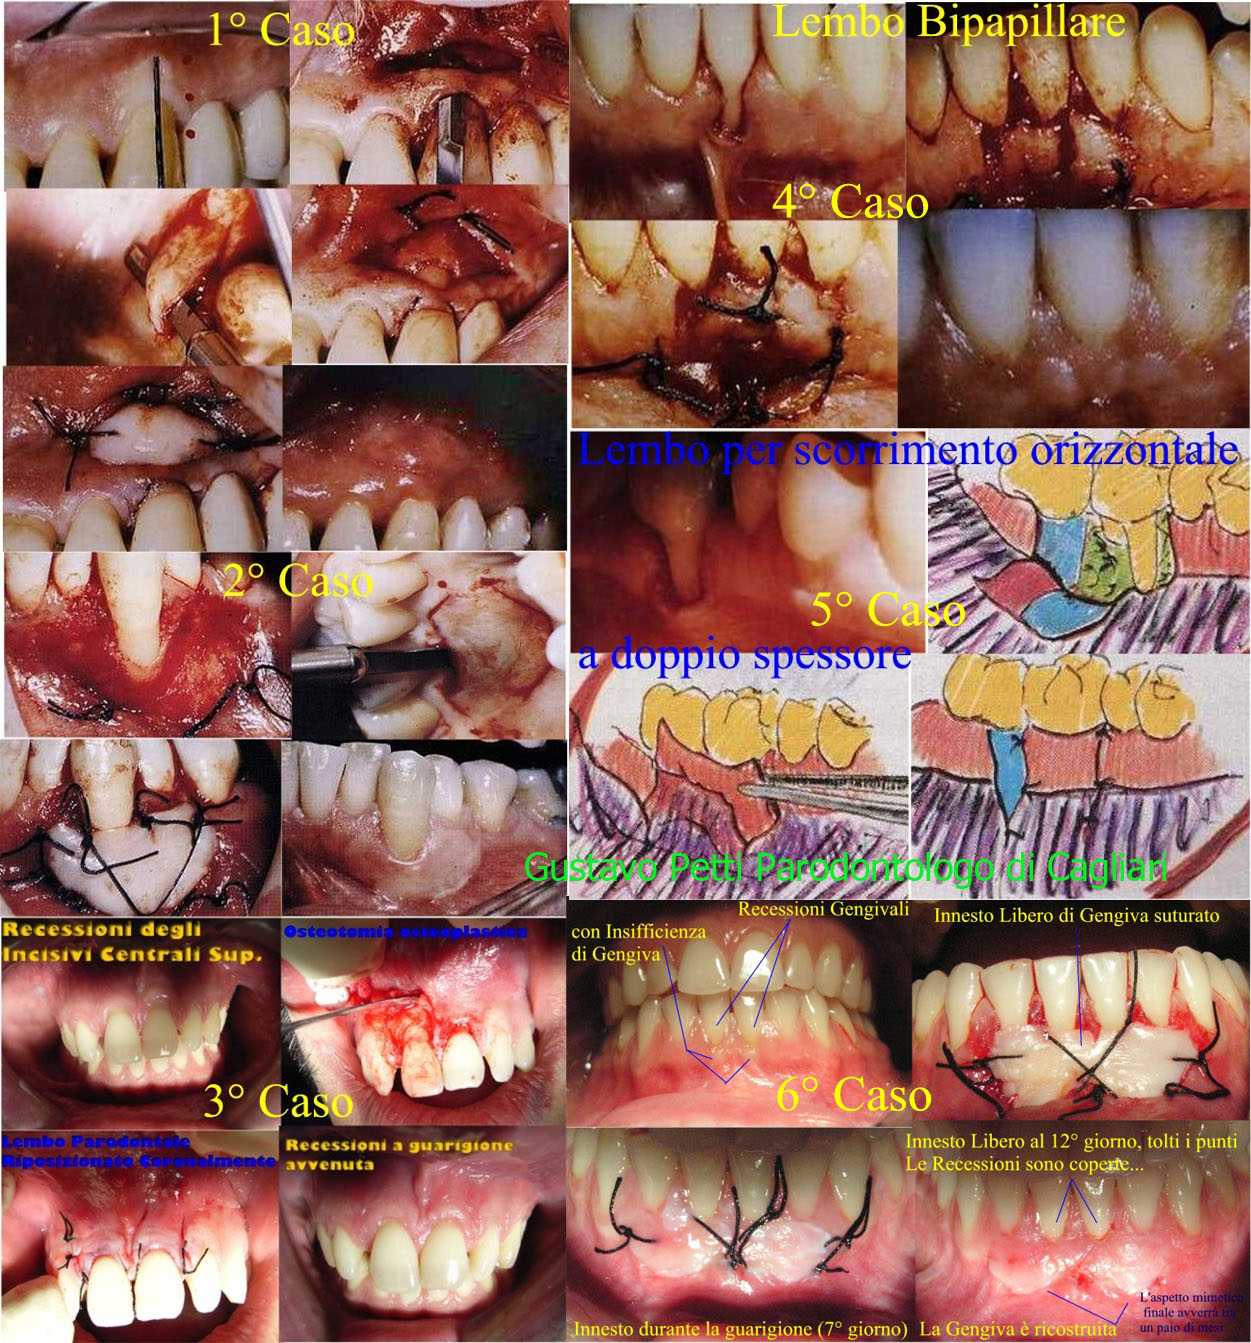

2-Da quanto dice si evince che Lei dovrebbe avere delle erosioni dello smalto, al colletto del dente e, contemporaneamente, delle recessioni gengivali! Bene, l'errore più comune che viene fatto in questi casi è quello di curare prima le erosioni mentre invece bisogna prima curare le Recessioni Gengivali e solo dopo le erosioni. Se si facesse il contrario, la gengiva non si attaccherebbe, perché troverebbe la struttura artificiale dell'otturazione e non la radice del dente in cui invece la gengiva ricostituirebbe l'attacco epiteliale e connettivale ricoprendo la recessione stessa con la chirurgia parodontale mucogengivale.

3-Bisogna fare una visita mucogengivale per le Recessioni stabilendo soprattutto la quantità e qualità di Gengiva Aderente Presente e la Profondità del Fornice, in tutta la bocca. In parole semplici, intorno al dente, ci deve essere la Gengiva Rosa che circonda i denti e che aderisce all'osso sottostante e non la mucosa Alveolare che è quella violacea, elastica, che forma il fornice e si riflette sulle labbra e le Guance. La cosa più importante è stabilire se ci sia o no insufficienza di Gengiva Aderente. La linea di giunzione mucogengivale, che separa la gengiva aderente dalla mucosa alveolare, non deve essere, praticamente, stata raggiunta dalla recessione. Se così fosse, invece, la salute del parodonto che sostiene il dente sarebbe compromessa perché la Mucosa Alveolare non è adatta a fungere da Gengiva Marginale e dare l'attacco epiteliale al dente e resistere ai traumi del bolo alimentare. In una recessione, quindi il primo e più importante "scopo" è quello di ricreare intorno al dente, una banda sufficiente di Gengiva Aderente. I problemi Estetici vengono "dopo" anche se importanti. Esistono interventi per raggiungere sicuramente il primo traguardo ed esistono altri interventi per raggiungere anche il secondo. Basta fare una corretta Diagnosi ed una Corretta Terapia. Le spiego qualcosa sulle Recessioni Gengivali. Questo lo si può decidere solo clinicamente con adeguata visita parodontale. Diciamo che ogni Recessione ed ogni zona della bocca necessitano di interventi adatti e mirati! Questa è serietà! Non si vende il "fumo", si vende "l'arrosto"! :) Infatti la morfologia delle recessioni è varia: possono assumere l'aspetto di fessure verticali che attraversano la banda di gengiva aderente (fessure di Stilman), oppure di perdita parziale o totale della gengiva aderente che ricopre la radice. La classificazione più comune è quella di MILLER, che prende in considerazione l'aspetto clinico e lo stato osseo interprossimale, in particolare delle piramidi ossee sottopapillari: prima classe ; recessioni che non si estendono fino alla giunzione mucogengivale e nelle quali non vi è perdita di osso e di tessuti molli interprossimali. seconda classe ; recessioni che raggiungono o superano la giunzione mucogengivale, non vi è perdita di osso e di tessuti molli interprossimali terza classe ; recessioni che superano o raggiungono la giunzione mucogengivale con perdita di osso o tessuto molle apicalmente alla giunzione amelocementizia, ma coronale all'estremità apicale della recessione. quarta classe ; recessioni che superano la giunzione mucogengivale con perdita ossea interprossimale fino ad un livello apicale rispetto alla base della recessione. La scelta del trattamento Ogni recessione ha il suo intervento d'elezione: i parametri più importanti da valutare, a tale proposito, sono l'integrità dell'osso alveolare e la qualità del tessuto aderente. E' ovvio che se non esiste deiscenza alveolare, la condizione è senz'altro più stabile che non se esista invece la deiscenza. Non tutte le recessioni vanno quindi curate :)